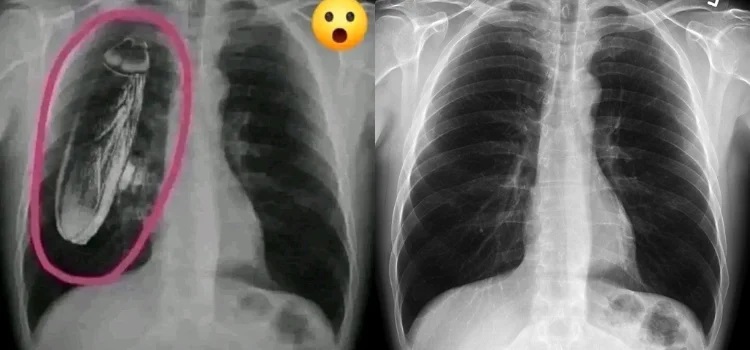

İddiaya eklenen fotoğraf tersine görsel arama yöntemiyle arandığında, “hamam böceğinin” fotoğrafa sonradan eklendiği anlaşılıyor. Fotoğrafın aslı standart bir göğüs röntgeni.

İki görsel karşılaştırıldığında, böceğin sonradan eklendiği de görülüyor.

Orijinal görüntü 22 Ocak 2010’da bir radyoloji görüntüleri deposu olan “Radiopedia” üzerinden yayınlanmış.